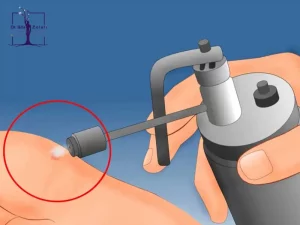

تست پاپ اسمیر چیست و چگونه انجام می شود؟

چه کسانی باید آزمایش پاپ اسمیر بدهند؟ به طور کلی